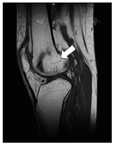

患者,女性,63岁,主因"反复腰腿疼痛14年"入院。患者于2006年因"特发性血小板减少性紫癜"使用大剂量激素治疗(强的松每日12片间断服用约1年的时间)后出现腰背部及腿部疼痛,逐渐加重至不能行走,就诊于华西医院内分泌代谢科后诊断为严重骨质疏松症,予以阿仑膦酸钠片、阿法骨化醇及钙尔奇D3治疗后疼痛症状缓解。6年前(2014年)无明显诱因出现双膝关节疼痛明显伴活动受限,完善CT及MRI(磁共振成像)提示膝关节上方股骨远端骨质破坏,髓腔内密度不均成地图样改变,多系骨梗死(图1)。收入内分泌代谢科后予以唑来膦酸(密固达)、普通维生素D3、钙尔奇D3和阿法骨化醇治疗后双膝关节疼痛逐渐缓解。此后患者分别于2015年9月24日、2016年10月14日、2017年12月13日、2019年2月28日及2020年5月30日,先后共6次输注唑来膦酸抗骨质疏松治疗。经治疗后患者双膝及腰背部疼痛明显缓解(VAS评分0分),双膝活动自如。2020年5月复查MRI提示:右股骨远端、右侧髌骨内见不规则地图样混杂信号影,与2014年比较,水肿影消失,病灶缩小且边界清楚(图2)。患者经过6年唑来膦酸治疗,双能X线吸收检测法(DXA)骨密度提示腰椎骨密度能够维持并较前有一定增长(图3),L1-4平均值增加2.5%,股骨颈及全髋分别降低约8.7%和7.8%。骨转换标志物也控制在较低水平(表1),从中也可以观察到唑来膦酸对于骨吸收的抑制作用远大于对骨形成的抑制。

注:MRI:磁共振成像